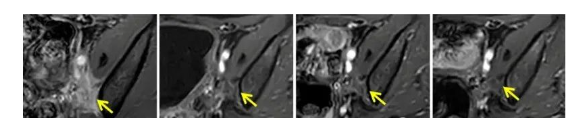

案例4:

一位处于Ⅲc期的宫颈癌患者在接受了根治性子宫切除术和盆腔淋巴结切除术后,又完成了4个周期的化疗。然而,在17个月后,她的癌症复发了,并且转移到了膀胱。但幸运的是,她在接受了TIL输注后仅10周,就再次达到了完全缓解的状态。